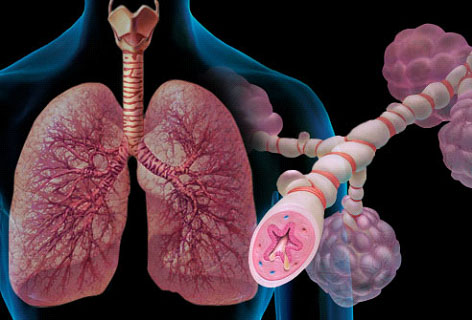

Κοροναϊός : Υποδοχείς των πνευμόνων η ενδεχόμενη πύλη εισόδου του στον οργανισμό

Υπάρχει μια υποψία ότι ο κοροναϊός μπορεί να εισέρχεται στον οργανισμό μέσω κάποιων υποδοχέων στους πνεύμονες, και μάλιστα ίσως κάτι τέτοιο να είναι αυξανόμενο σε υπερτασικούς